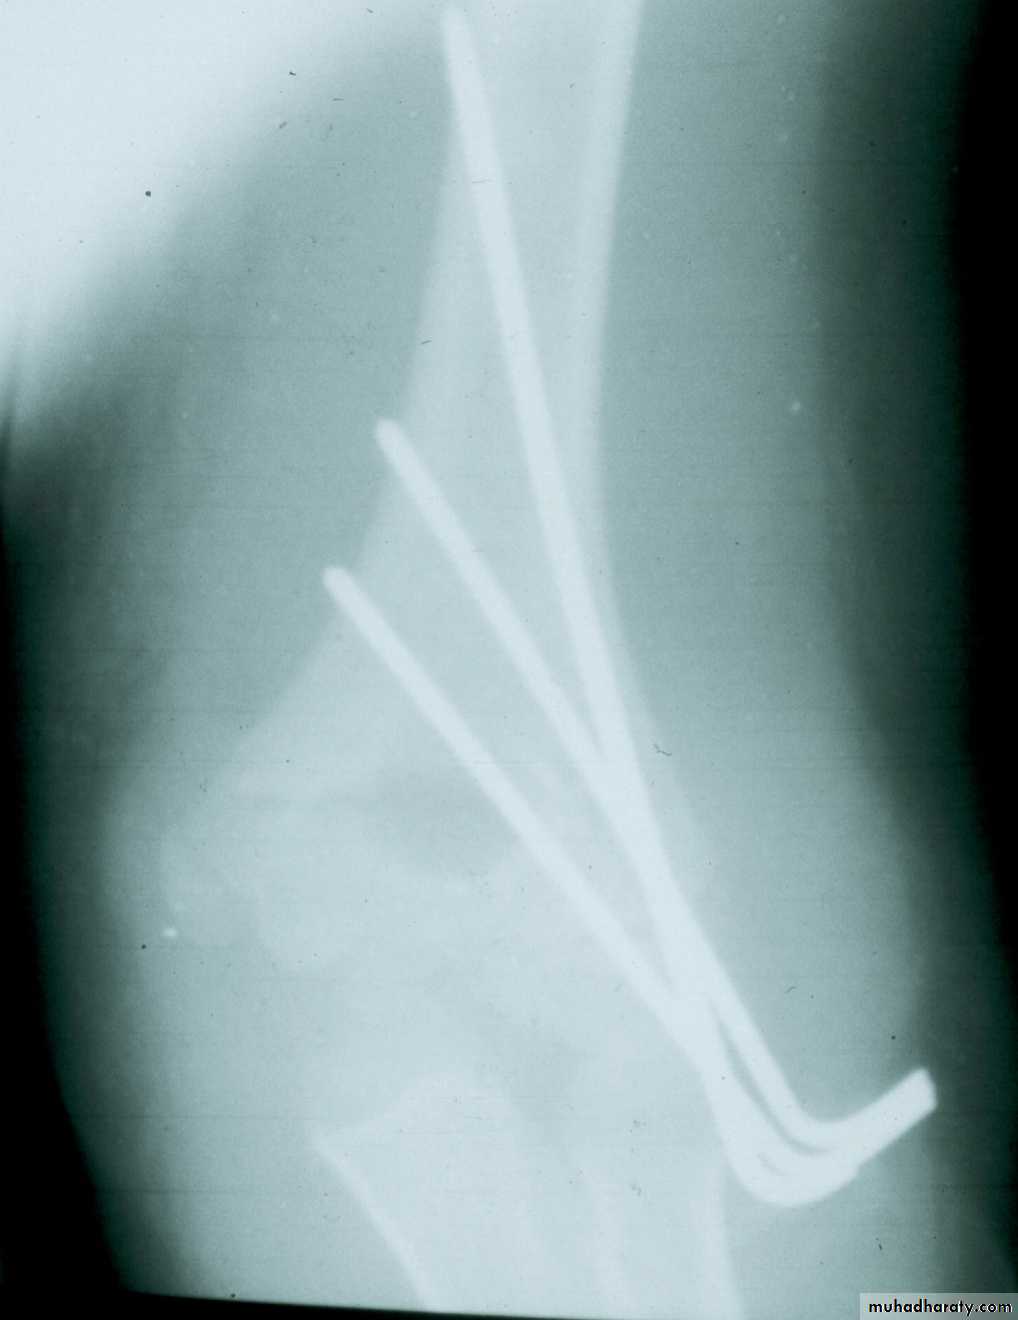

Percutaneous

pin

fixation

If a cast is inadequate,

then what is the standard for maintaining the reduction?

How can the rotational stability with lateral pin be enhanced?

By separating the pins

and adding a third pin.

Is there a way to put X pins

without producing this scar?Lateral Antegrade pin